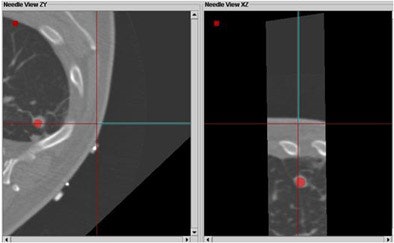

In two cases the researchers also successfully registered preprocedural CT scans with prior DICOM images. Registration with a prior MR scan was used for a renal radiofrequency ablation, and registration with a prior PET/CT scan was used to biopsy a lymphoma close to the heart, an organ that is critical to avoid during such procedures.

![]() |

| Registration with a prior PET/CT scan was used to biopsy a lymphoma close to the heart. |